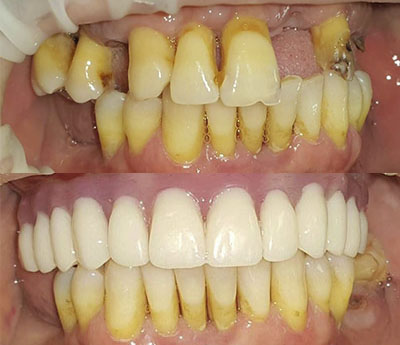

Il sistema Fast&Fixed è un'alternativa immediata. Questa procedura ti permetterà di ritrovare il tuo sorriso in un unico intervento. Il risultato è immediato e recupererai autostima e fiducia in te stesso.